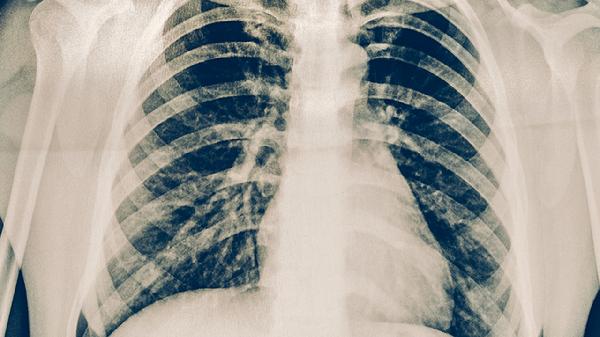

胸腔右侧肋骨下面疼痛怎么回事

胸腔右侧肋骨下面疼痛可能与肋间神经痛、胆囊炎、肋软骨炎、肝脏疾病、胸膜炎等因素有关,可通过热敷、药物治疗、手术等方式缓解。建议及时就医明确病因。

胸膜炎常由肺炎或结核引起,疼痛随呼吸加剧并伴胸腔积液。结核性胸膜炎需异烟肼片联合利福平胶囊抗结核,细菌性胸膜炎可使用左氧氟沙星片,大量积液需行胸腔穿刺引流。